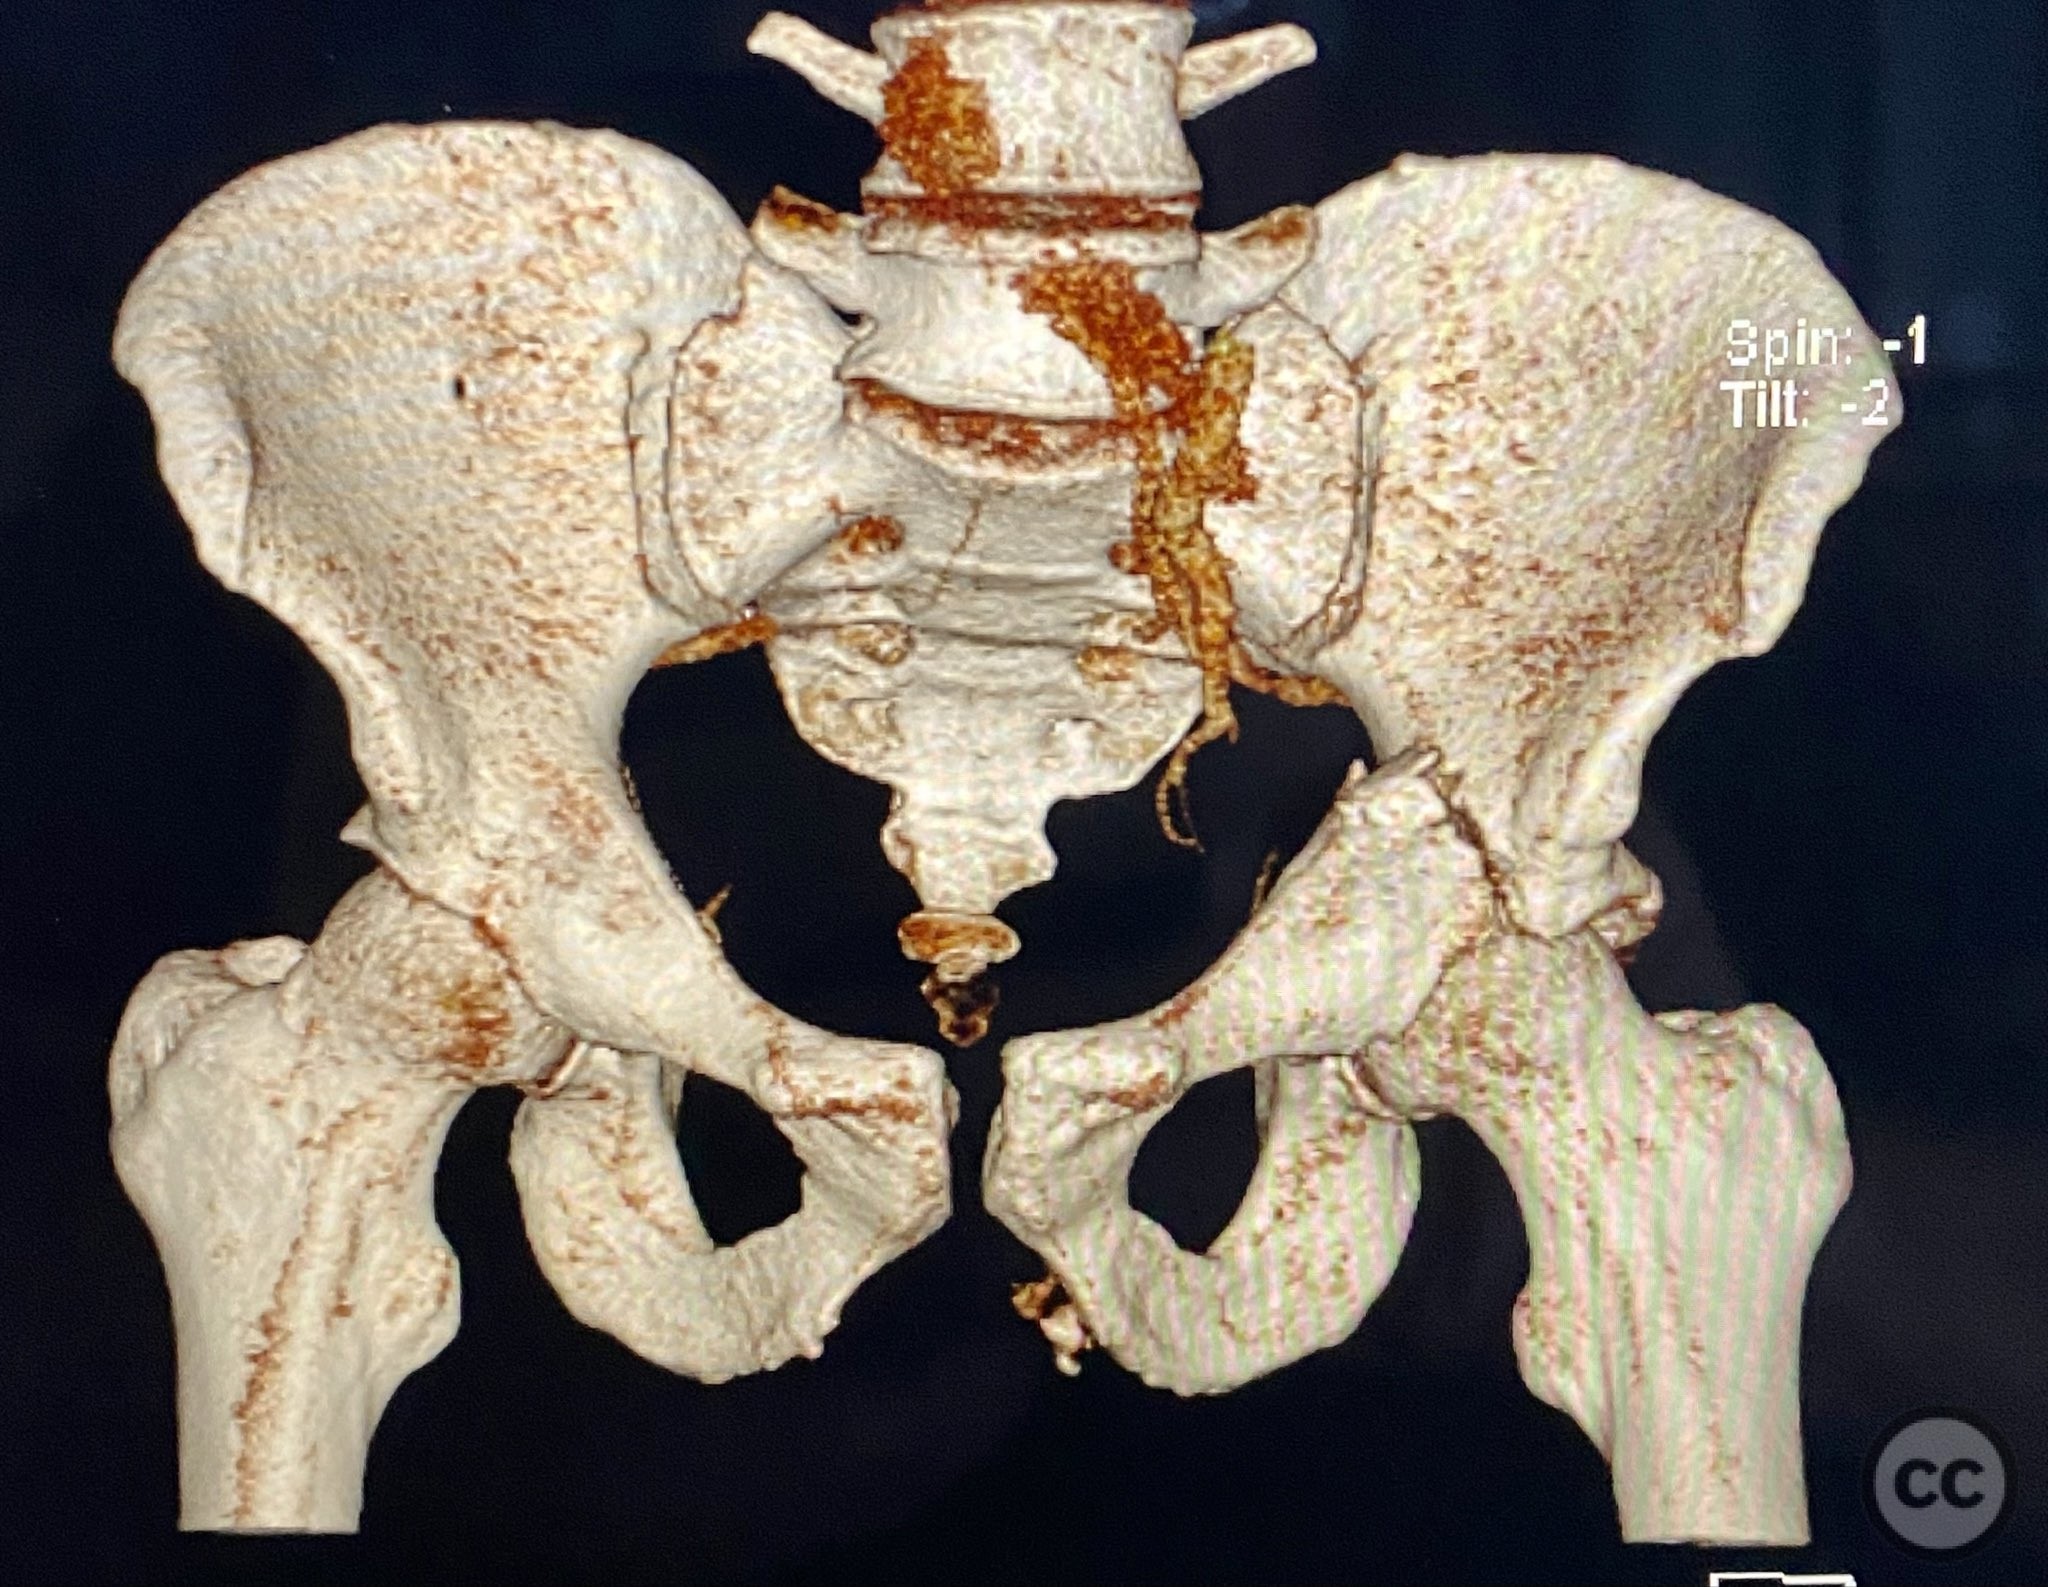

Clinical and radiological findings:  Adult male with a closed, comminuted left femoral shaft fracture and complex pelvic ring injury. Initial imaging demonstrated bilateral sacroiliac (SI) joint disruptions and a left-sided transtectal transverse acetabular fracture (Letournel-Judet: transverse type), with the fracture line exiting through the posterior wall region but without a discrete posterior wall fragment. The femoral head was displaced caudally, following the unstable distal acetabular segment, resulting in loss of congruency with the intact acetabular dome. There was also a symphyseal disruption. No associated abdominal, visceral, thoracic, cranial, or other injuries were present. Application of a circumferential pelvic binder resulted in visible changes in pelvic alignment on imaging. AO/OTA Classification: - Pelvic ring: 61-C1.3 (bilateral SI joint disruption, complete instability) - Acetabulum: 62-B1 (transverse fracture) - Femur: 32-C3 (comminuted diaphyseal fracture)